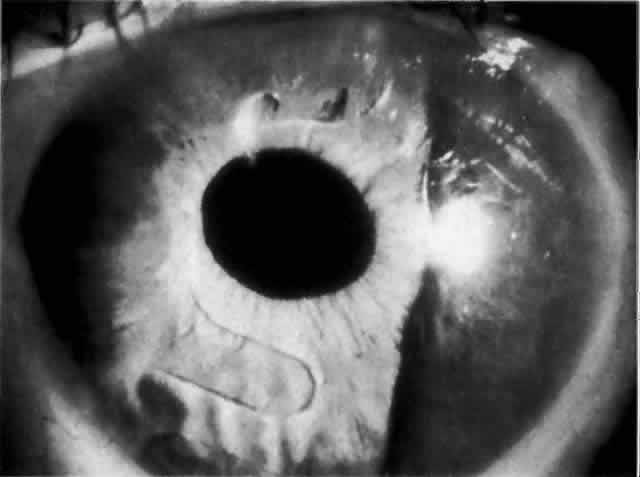

Cortical lens fragments retained in either the anterior chamber or the vitreous can also obstruct the trabecular meshwork in the form of free lens particles or macrophages swollen with lens material (Figs. 2 and 3). Glaucoma does not occur in all eyes that contain cortical remnants; the inflammatory response may be more pronounced and prolonged in eyes containing a higher amount of lens material. When inflammation is marked, keratic precipitates and sometimes a hypopyon may be present. Distinction between this sterile inflammatory endophthalmitis and infectious endophthalmitis can be difficult and may depend on the initial response to therapy. The presence or absence of IOP elevation is not helpful in making this distinction because IOP may be normal or elevated in both situations.